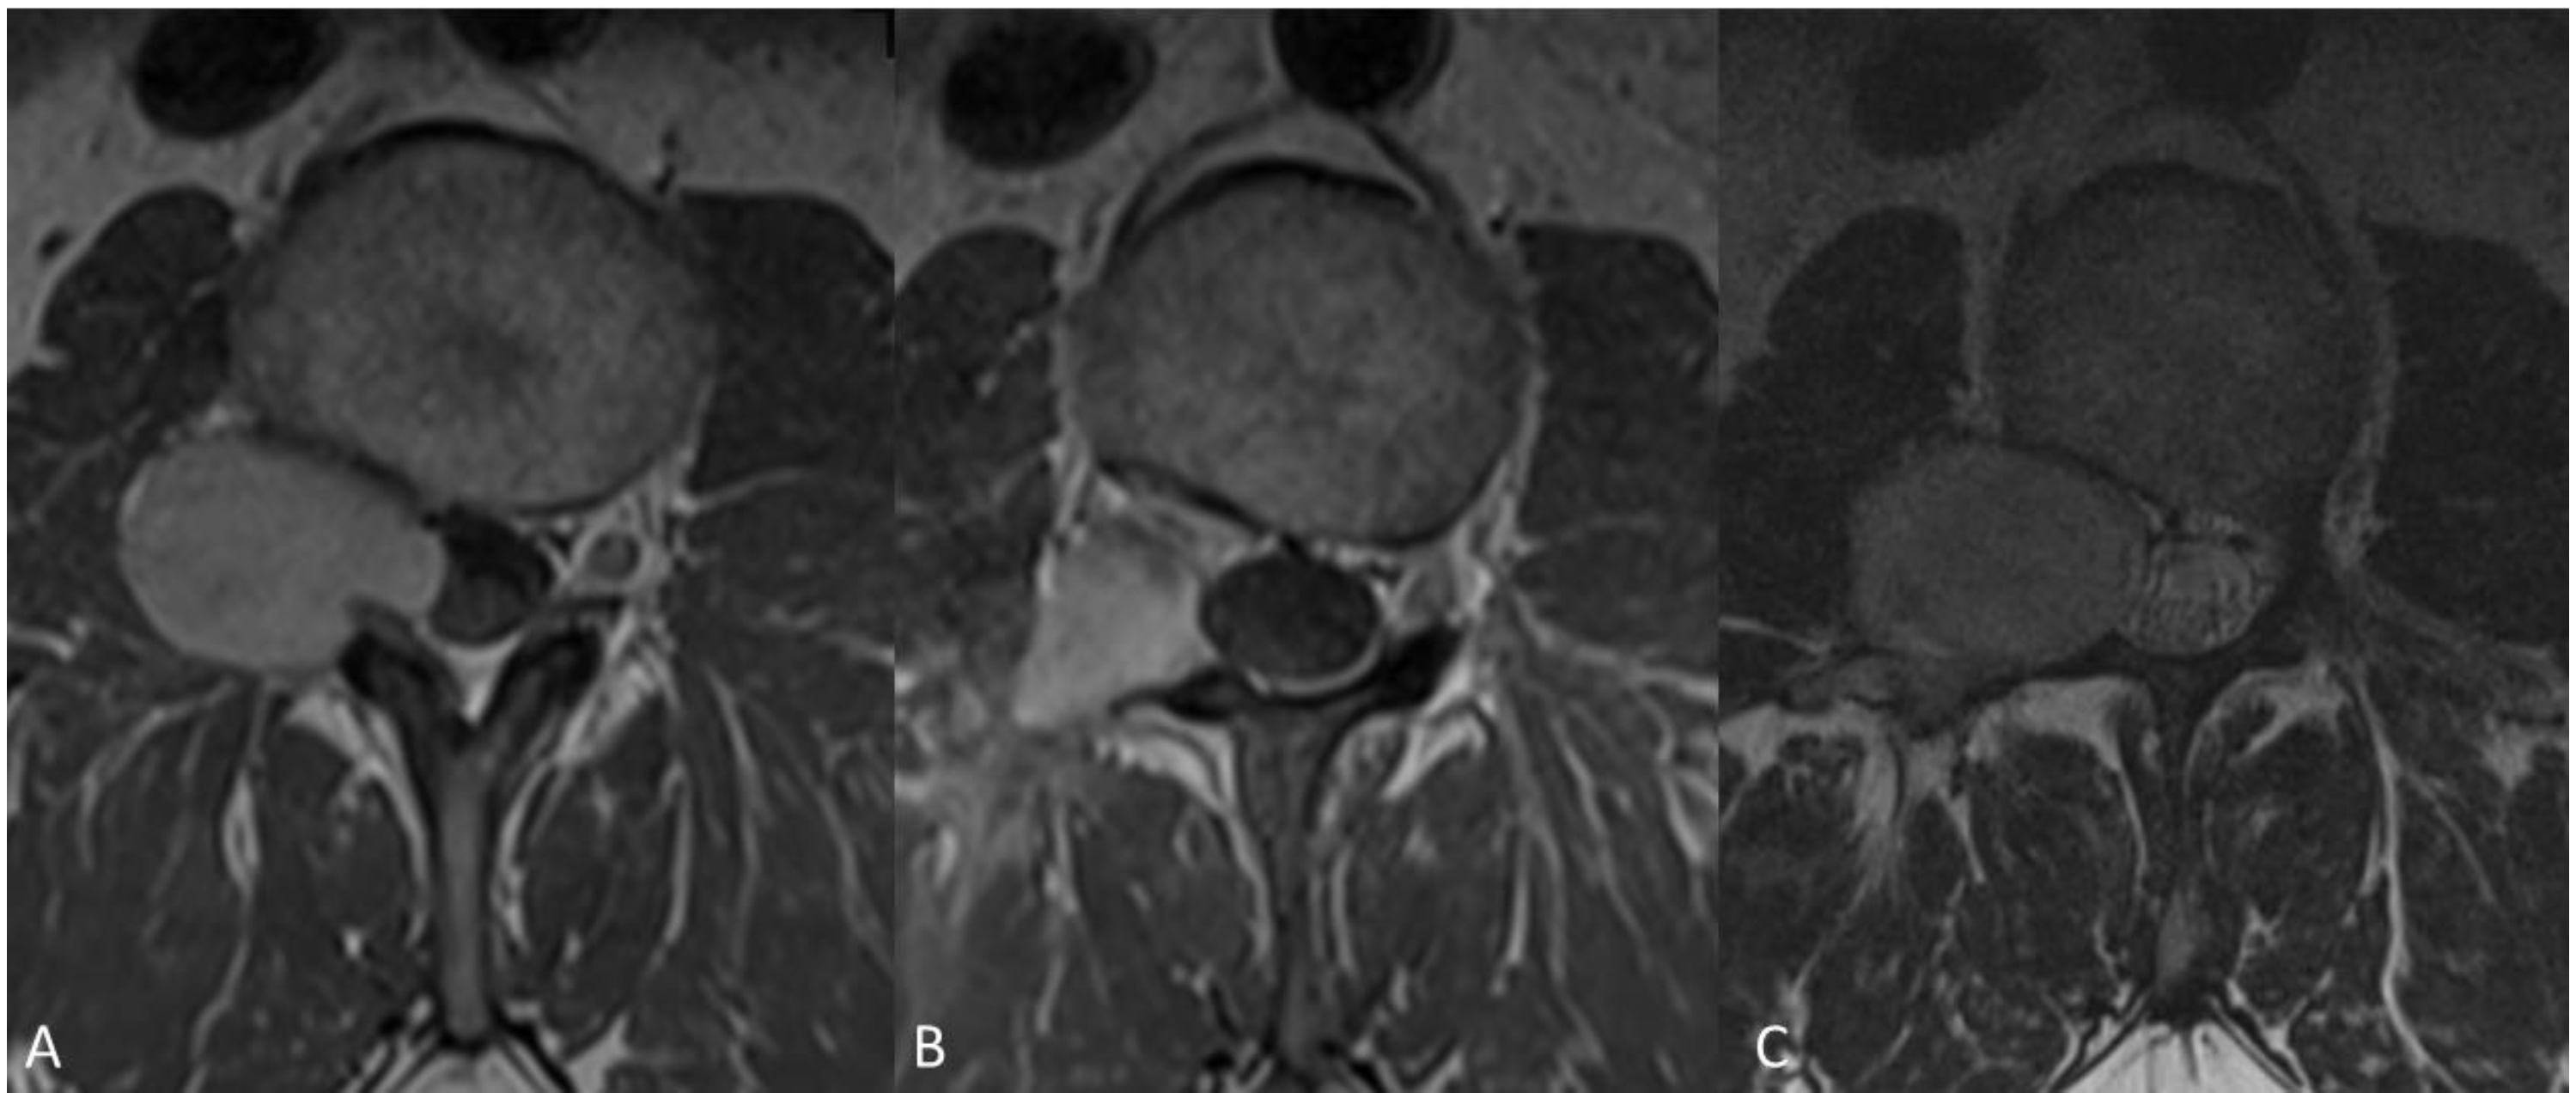

Case example of a 46-year-old male patient admitted with sciatica and low back pain. MRI demonstrated a space occupying lesion at the level of L 2–3, Eden type 3 (A), histology conformed a grade I schwannoma. Tumor resection was performed via dorso-lateral approach. Post-operative MRI, three months after surgery showed reduction of tumor volume with residual contrast enhancement (B) and patient was followed up. After a period of three years MRI demonstrated clear tumor progression (C) and patient had to be operated again.

Figure 5.